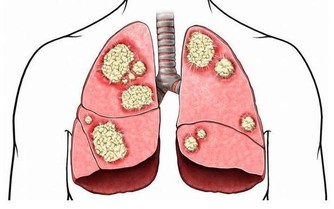

黑木耳富含的多糖膠體有良好的清肺功能,

對霧霾天氣吸入的有害雜質有很強的吸附作用,

可以緩解再霧霾天天吸入污濁空氣引起的咽部瘙癢,

霧霾天晚上吃點木耳做的菜非常有必要!

還具有一定的抗癌益氣止血止痛補血活血和治療心血管疾病功能等...........